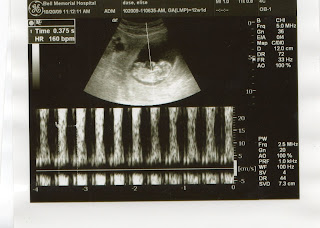

Just a little introduction to our little one to come. We had our first ultra sound today and things are looking good. We will find out next month weather its a boy or a girl so we are going to just have to wait but the doctor did say that if we had done this ultra sound just a week or so later she thinks she would be able to tell what it is , oh well .

the heart beat